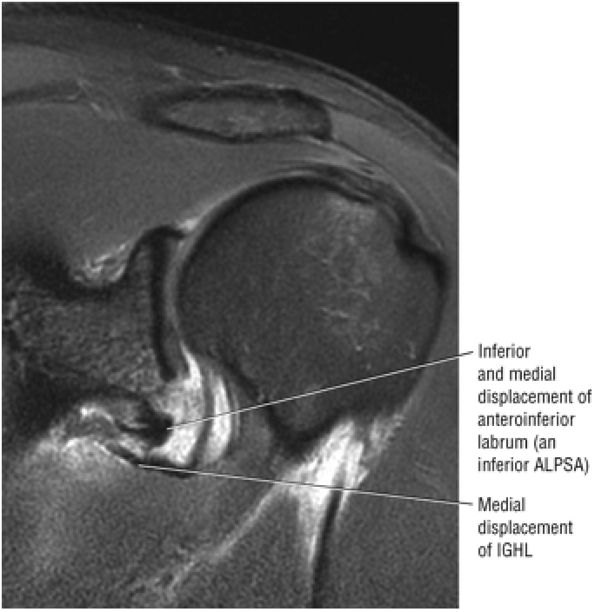

![]() |

|

FIGURE 8.151 ● (A) Coronal FS PD FSE and (B) sagittal FS PD FSE images of hyperintense muscle–tendon signal intensity associated with a large full-thickness acute rotator cuff tear. There is secondary superior ascent of the humeral head.